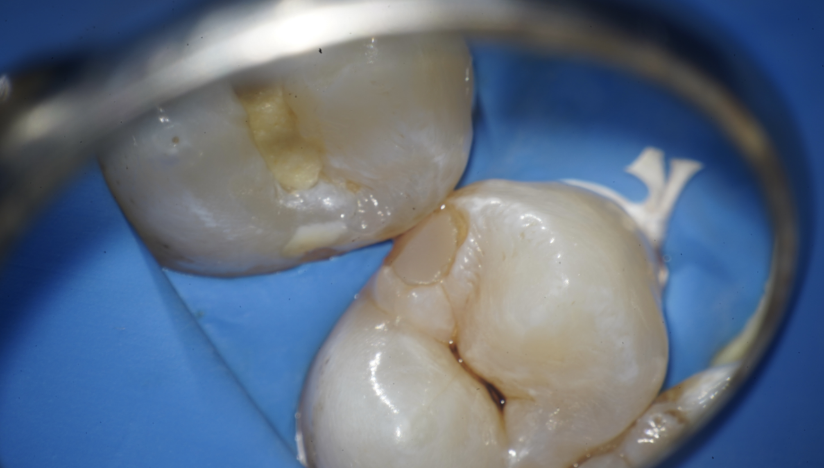

MIを意識しながら予防的拡大を行い

虫歯治療を完了させた症例

Before

After

主訴

虫歯の治療をしたい。

治療内容

セラミックアンレー2本

セラミックインレー1本

IDS(Immadiate Dentin Sealing)3本

治療期間

通院回数2回

治療費用

390,500

治療の

リスク

術後に一時的な知覚過敏症状が出る可能性があります。